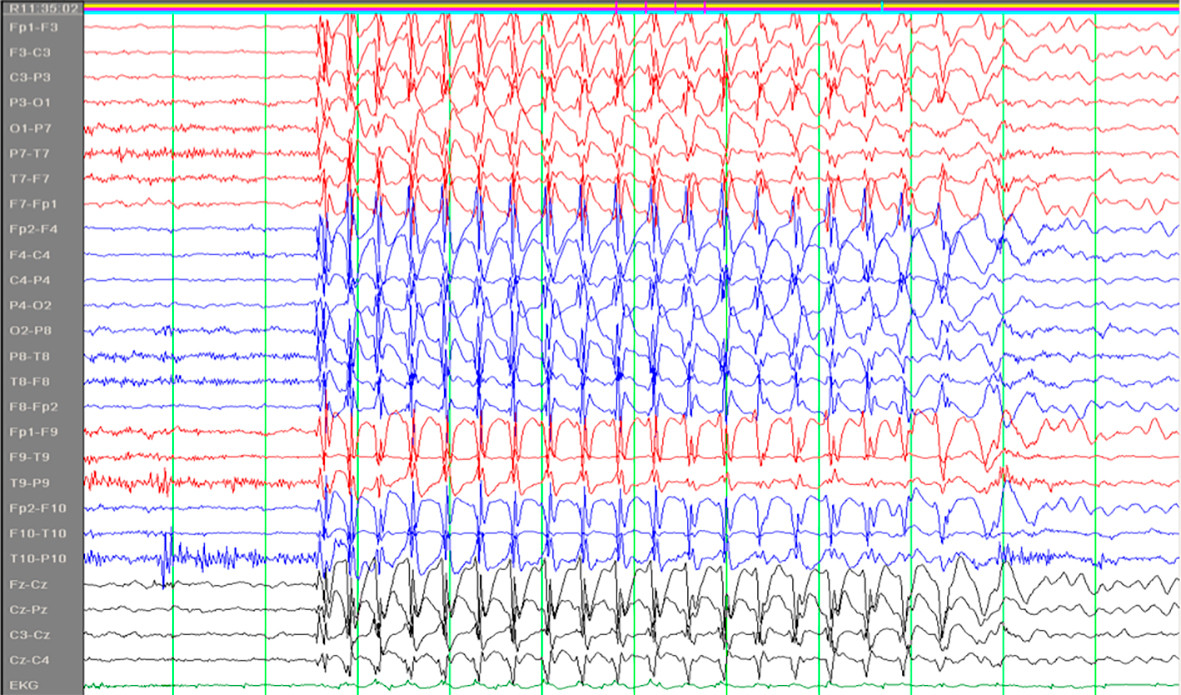

Absenser er en type epileptiske anfall som kan ses ved flere generaliserte epilepsiformer, først og fremst ved absensepilepsi i barnealderen. Ordet stammer fra det franske absence og det latinske absentia og kan oversettes med åndsfravær. Barna blir i noen sekunder fraværende i sin virksomhet eller tale, uten at vedkommende selv merker det. De får et tomt, stirrende blikk. Det er ingen kramper, men av og til ses diskrete rykninger i øyelokkene. Det er viktig at foreldre er oppmerksomme på slike tilfeller hos barn. Absensene har et spesifikt EEG-korrelat; 3/sekund «spike-waves» (fig 1) (1).

Absensbegrepet bør reserveres til den spesifikke anfallsformen som er nevnt over, og som er ledsaget av nevnte EEG-korrelat. Er man som kliniker usikker på hva slags anfall pasienten har, bør man heller beskrive anfallet med ord som episoder med fjernhet, manglende kontakt, redusert bevissthet e.l.